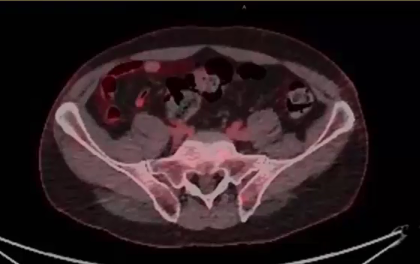

PSA, PSMA, PET scan, regional nodes, external iliac artery, right and left obturator, left perirectal, rib trauma, Zytiga, Lupron, bladder preservation, rectum, 60 Gy, toxicity, SIB, abdominal GI cramping, diarrhea, urology, ADT, prostate, salvage brachytherapy, SBRT, ASCENDE-RT trial, brachy boo...

metastatic prostate cancer, back pain, retroperitoneal adenopathy, Degarelix, Xtandi, Taxotere, Docetaxel, Prednisone, side effects, PSMA PET CT, avid expression, left sacral ala, castration resistant, ADT, tumor genomic profile, immunotherapy, homologous repair defect, urinary symptom palliation...